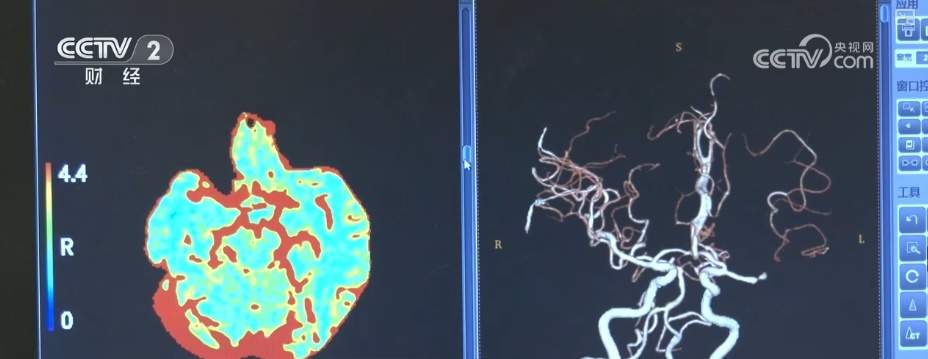

天坛医院的“AI医生”被称为急性脑卒中智能影像决策平台。脑卒中患者到院后,首先进行平扫CT和增强CT等检查,经过上千张影像检查图片的分析,“AI医生”可进行颅内出血和缺血等鉴别分析,可以直观勾勒出血区域,并进一步提示出血类型和血肿扩大风险概率。